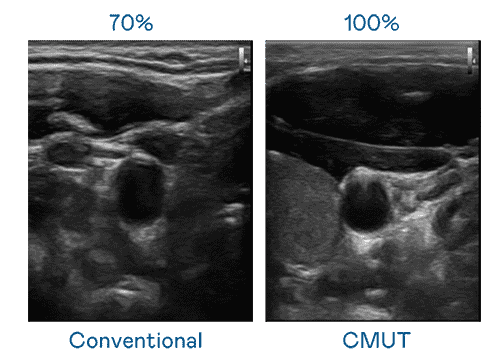

CMUT 技术是一种用电容式微机电元件来产生超音波讯号的技术。。与传统 PZT 压电式技术相比,,,,CMUT 频宽增加 30%,,,更宽频的超音波讯号让影像解析度大幅提升,,,是实现高影像品质医疗超音波扫描、、促进精准医疗发展的关键技术。。。

大频宽带来超清晰影像

超音波影像的解析度高低,,首先取决于探头能发出的讯号频宽。。。。人生就是博 CMUT 可提供高清晰的超音波讯号,,提供高频宽、、高灵敏度、、影像纹理细节更高的超音波影像,,协助医护人员缩短影像判读时间及利用精准的医疗影像进行诊断。。